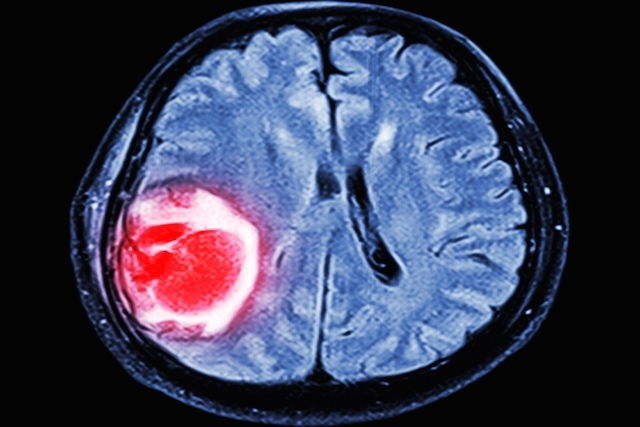

blood clot in the brain on imaging

The provider will usually order a complete blood count (CBC), coagulation testing, and a D-dimer level. Imaging tests may also be needed, such as magnetic resonance imaging (MRI), computed tomography (CT scan), angiography, venography, and/or ultrasound to look for a clot and/or brain changes suggestive of thrombosis.